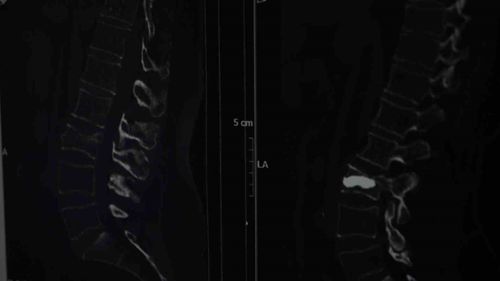

İstanbul'da 76 yaşındaki Alis Armağan düşme sonrası ağrılarını bel fıtığı sandı; tetkikte omurga kırığı ve osteoporoz tespit edildi, 25 Ağustos'ta kifoplastiyle iyileşti.

Kemik Erimesi Uyarısı: 76 Yaşındaki Hastanın Omurga Kırığı Bel Fıtığı Sanıldı İstanbulda yaşayan 76 yaşındaki Alis Armağan, düşme sonrası hissettiği ağrıları bel fıtığına bağladı. Yapılan tetkiklerde ise omurgasında kırık ve kemik erimesi (osteoporoz) saptandı. Hastaya 25 Ağustos'ta uygulanan kifoplasti operasyonu…